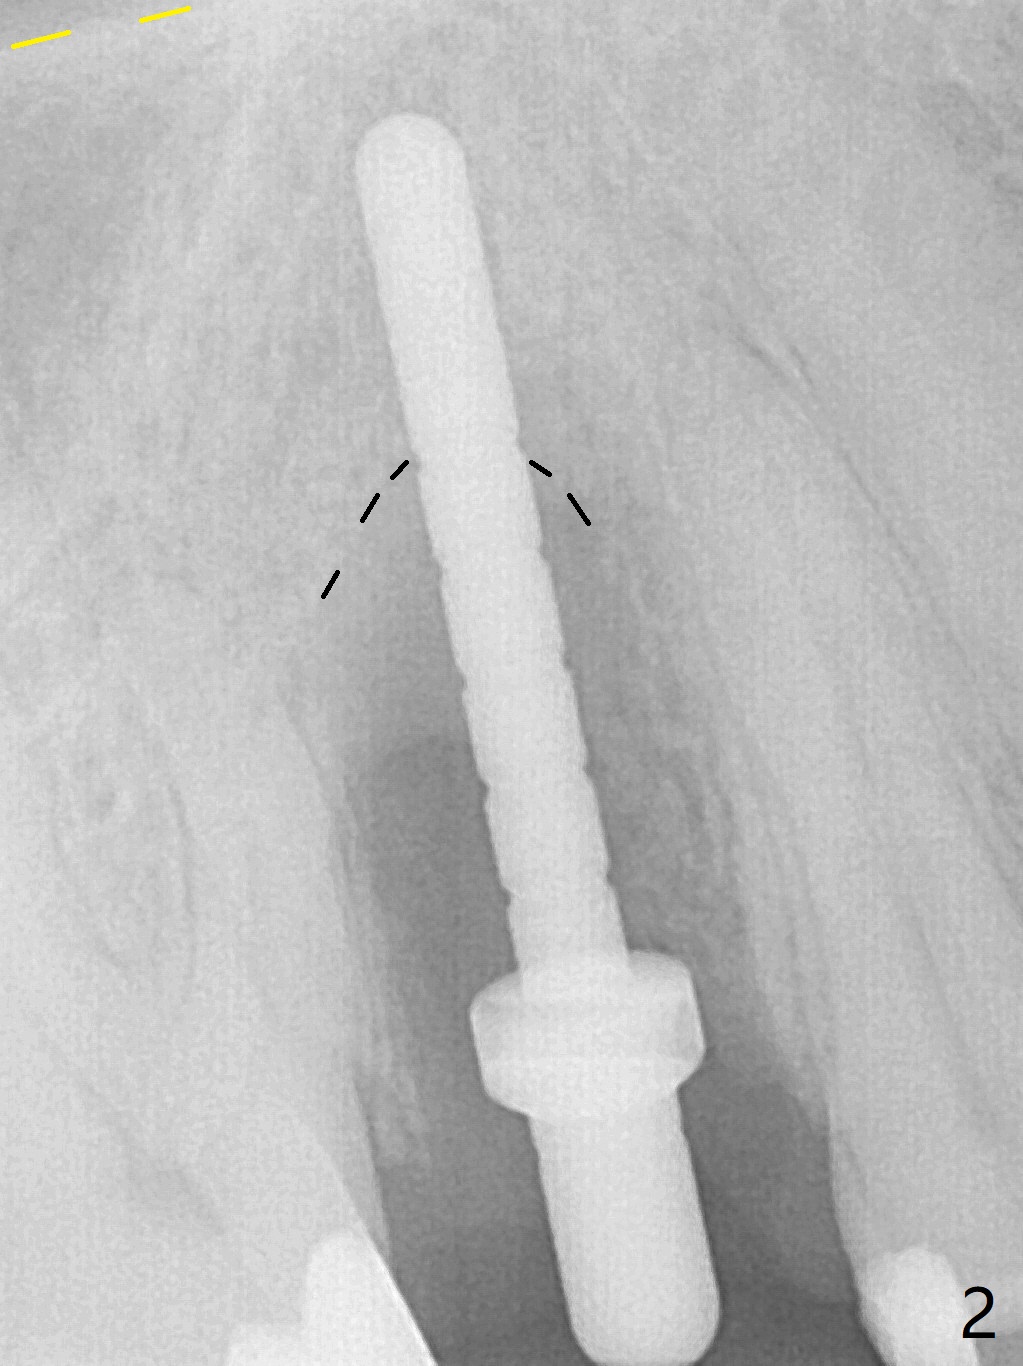

When the tooth #4 with vertical root fracture (Fig.1) is extracted, the buccal plate is found to be lost. The lowest point of the defect is shown as black dashed line in Fig.2 (yellow dashed line: sinus floor). After use of 2.5 mm reamer for 21 mm (buccal gingival level) and 3.0 mm reamer for ~17 mm, a 3.8x15 mm dummy implant is placed with 30 Ncm and 1.85 mm apical space (Fig.3 pink outline). A 3.8x18 mm (definitive) implant is placed with <40 Ncm with the implant plateau apical to the lingual crest (Fig.4,5). The buccal plate defect is repaired by Vanilla Graft (Fig.6 *) before and after insertion of a 4.5x4(3) mm abutment. The buccal plate defect seems to being repaired 4 months postop (Fig.7). Occlusal wear suggests bruxism, which is also associated with the root fracture. Night guard is recommended. The defect repair is close to completion 8 months post cementation (Fig.8). The crown/abutment is found to be loose 1 year 4 months post cementation and retightened without checking whether there is clinical 2nd DO caries of #3 (Fig.9, "sensitive to water pik"). A few days later, DO composite is being removed. It is difficult to determine whether the 2nd DO caries or gap has been removed with the neighboring crown in place. When the crown/abutment is removed and gingival retractions are inserted, there is no decay. The gap is removed. With Toflemire in place, the crown/abutment is reseated and hand tightened; after packable composite, the crown/abutment is removed, there is no more DO gap.